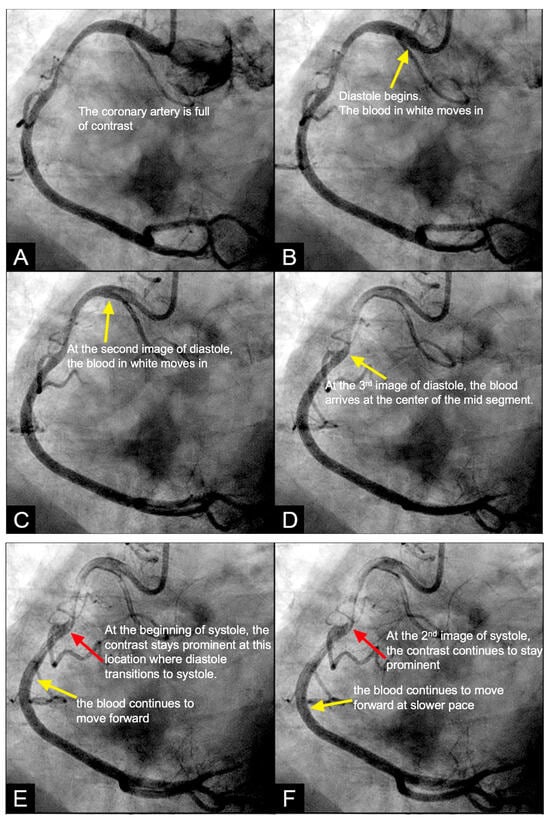

The secondary objective was to examine the relationship between antinodes and the presence of coronary stenoses, as well as between nodes and minimally diseased or lesion-free coronary segments. Ultimately, the investigation aimed to establish antinodes as potential markers for high-pressure surges linked to intimal damage. These locations of antinodes are used to construct a coronary acoustic activity (or action) map, enabling the identification of existing lesions, forecasting the progression of current lesions, and predicting the development of potential future lesions. Table 5 outlines the protocol on how to identify and label the five zones of compression and rarefaction (antinodes) and the minimal or lesion-free segments (nodes) within the coronary arteries. The protocol to identify the antinodes of compression and rarefaction and the nodes in between the antinodes uses the novel coronary dynamic angiographic technique. The protocol is listed in Table 5 and Figure 16A–E.

Table 5.

Protocol to identify the first antinode of compression.

Figure 16.

(A–D) These are four consecutive coronary images. (A) The blood in white begins to move in at the beginning of diastole (1D). (B) The blood in white is seen moving to the proximal segment of the right coronary artery (RCA) (2D). (C) The blood arrives at the center of the mid-segment of the RCA. (D) The blood in white is seen to advance a little more, reaching the lesion at the mid RCA. (E) This is the fifth image of the sequence from diastole to systole. From (A–D), the blood moves in rapidly in diastole. (E) The blood is stopped abruptly due to water hammer shock. The contrast concentration is more prominent at the location 1, where the retrograde pressure wave at the beginning of systole collides with the tip of the antegrade flow of diastole. The blue arrow shows a place where contrast is concentrated at the end of diastole. At the same time, the pressure wave reflects at the speed of sound, the anti-node 4 at the open end of the coronary artery could be seen early.

FIRST Compression Zone with High Contrast Concentration. Angiographic Identification. During diastole, coronary blood flow reaches a relatively high velocity. At the onset of systole, the contraction of the left ventricle abruptly interrupts this flow, triggering a water hammer effect. This results in the formation of a retrograde pressure wave, which collides with the antegrade flow at a critical timing when diastole transitions into systole. The initial reflection point, designated as location 1, is characterized by pockets of prolonged concentration of contrast agent, seen as a disorganized mixing of dark (contrast) and light (blood) materials (blue arrow in Figure 16E). These black-and-white pockets may signify turbulent flow, mirroring the surge of pressure in the local area (Figure 16A–D).

Mechanism of Damage. At location 1, damage mechanisms are likely driven by localized pressure spikes, stress concentrations, or repeated high-pressure cycles (vibrations), which induce deformation, cracking, or microtears in the intimal layer. These disruptions facilitate the migration of low-density lipoprotein (LDL) cholesterol into the subintimal space, initiating the atherosclerotic cascade (blue arrow in Figure 16E).

Clinical Relevance. The lesion at this location is very important because this is the most common lesion in the right coronary artery (RCA) and the most common location for ST elevation myocardial infarction in the RCA [35]. The reason is because this is the location where the pressure wave from water hammer hits first in its retrograde reflection, when diastole transitions to systole.

CRITICAL THINKING. High Concentration of Contrast at location 1 as a Marker of Compression Activity. During a typical cardiac cycle, antegrade blood flow accelerates during diastole and transitions rapidly into the systole, initiating a water hammer phenomenon that generates a retrograde pressure wave. This retrograde wave propagates at nearly the speed of sound and undergoes multiple reflections within one or two diastole–systole cycles along the length of a coronary artery. These reflections produce hundreds of retrograde pressure waves, which may synchronize with antegrade waves to form resonant patterns or, conversely, cancel out. The wave reflections occur at distinct locations: the diastole-to-systole junction (location 1), the coronary artery ostium (location 4), and the systole-to-diastole junction (location 2). The resulting wave dynamics display features of acoustic resonance, with regions of high contrast concentration corresponding to antinodes—pressure peaks associated with arterial damage or the progression of atherosclerosis (Figure 16E). High-contrast regions at locations 1 and 4, observed in coronary angiography, likely represent zones of compression and rarefaction, indicative of pressure surges that may compromise the intimal layer. The critical challenge lies in determining how these observations and hypotheses can be rigorously validated.